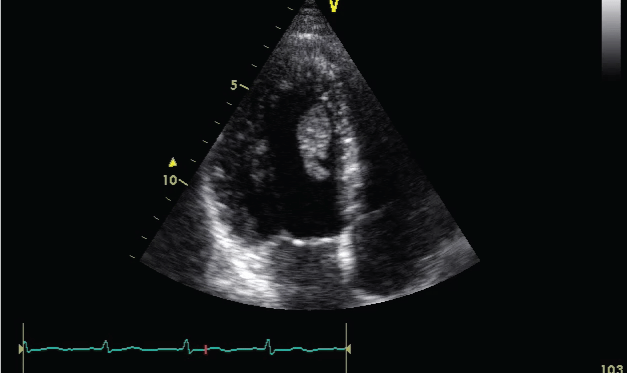

Echocardiographic examination (Figure 1) revealed isodense mobile mass attached to left ventricle apex, moving in every systole towards the left ventricle outflow tract. Left ventricular segmental wall motion abnormalities weren't detected by echocardiography. Blood analysis were performed to determine any diseases predisposing to thrombosis formation (antithrombin III, activated protein C resistance, Protein C and Protein S, Lupus anticoagulants, rheumatologic markers, erythrocyte sedimentation rate, full blood count including eosinophil count) and imaging studies were performed to rule out malignancies, but nothing could be found. Surgical excision of this mobile mass was planned because of high risk of embolization. Preoperative coronary angiography revealed chronic dissection and severe stenosis at right coronary artery with TIMI 3 distal flow. Surgical excision of the mass (Figure 2) was performed without any complication, and the patient was discharged with antiplatelet and oral anticoagulation treatment.